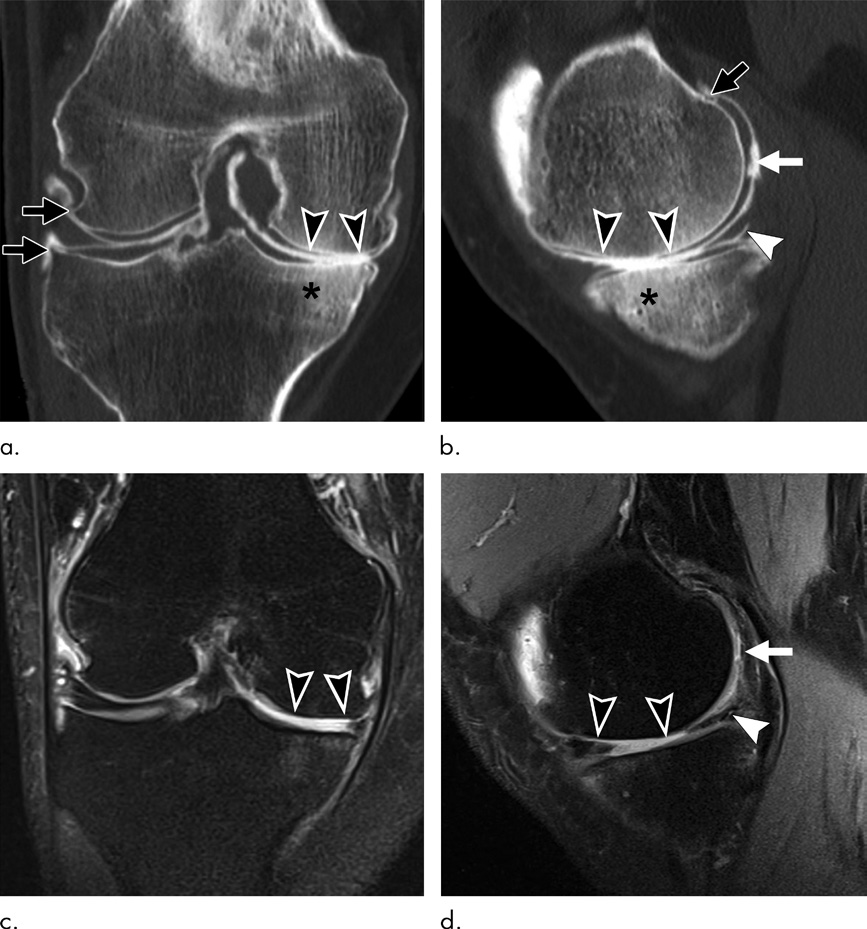

- CT关节造影(CTA):经关节内注射造影剂后,可精准评估软骨厚度、 focal软骨缺损、半月板撕裂、韧带损伤(如前交叉韧带撕裂),是软骨厚度测量的“金标准”之一(图3),且能通过无创方式评估软骨糖胺聚糖含量。

3. 局限与适用场景

- 局限:有电离辐射(不适合孕妇与儿童)、CTA为有创操作(需关节穿刺)、对软组织(滑膜、骨髓病变)的评估能力弱于MRI;

- 适用场景:OA生物力学评估(负重位/4D CT)、钙化相关OA诊断(双能CT)、软骨修复术后随访(CTA评估修复组织厚度)。